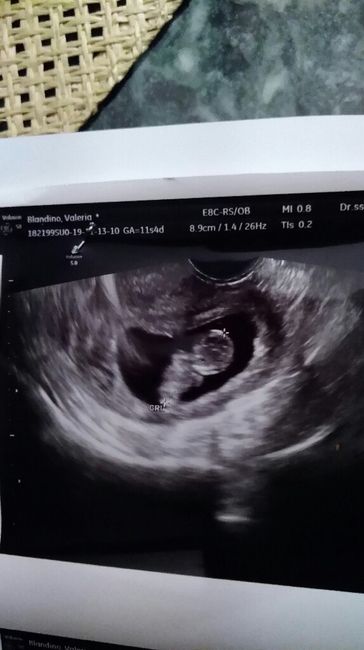

Buongiorno ragazze,voglio aggiornarvi sulla crescita del mio fagiolino. Ieri ho fatto l'eco per il bi test e la ginecologa si è sbilanciata sul sesso. Parrebbe una femminuccia ma non è questo l'importante. La piccola o il piccolo sta bene,si muoveva...

Ho caricato una foto nel post di Valeria

2348 giorni fa

Ciao ragazze oggi ho fatto l'eco,sono a 9+4 e tutto procede bene. La paura c'è sempre ma la gine è stata molto carina e comprensiva. Ecco il mio fagiolino. Che dite?maschietto o femminuccia?

2373 giorni fa